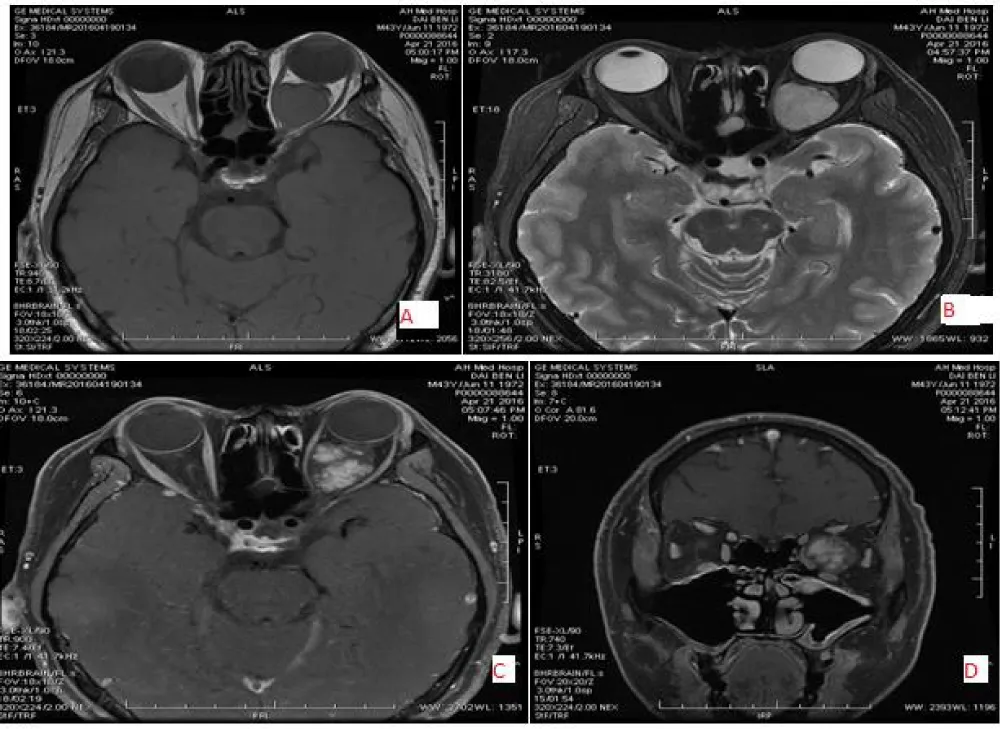

The extraconal space is located between the outside of the extraocular muscles and the inside of the orbital periosteum. In this space, mostly inflammatory and infectious diseases are seen. The inflammatory tumors include Graves’ disease, pseudotumor, granulomatous inflammation, and infectious diseases such as cellulitis and sinusitis. Orbital inflammatory pseudotumor is an idiopathic, benign, non-infectious inflammatory tumor in the orbit, with unknown causative factors. It presents with common signs and symptoms of a painful and unilateral mass, helping to distinguish it from thyroid-associated ophthalmopathy. It is usually a diffuse type of inflammatory disease and can be challenging to differentiate from other inflammatory diseases and neoplasms. However, a quick response to a trial of steroid therapy may aid in the diagnosis. Orbital lymphoma can be challenging to distinguish from orbital pseudotumor. Lymphoma is typically seen as decreased density on delayed images in dual-phase spiral CT contrast, while orbital pseudotumor is mostly seen as increased density on delayed images in dual-phase CT contrast [21]. Orbital lymphoma typically shows a brighter DWI signal and lower apparent diffusion coefficient (ADC) than normal orbital structures, whereas orbital pseudotumor shows intermediate DWI and ADC signal similar to the normal lacrimal gland [22]. Other tumors that can be found in this area include pleomorphic adenoma, adenoid cystic carcinoma, non- Hodgkin’s lymphoma, metastasis, and abscess (Figures 5-7).

Download Image

Figure 7: 39-year-old female with left-sided Inflammatory pseudotumor, located in the extraconal and inferolateral region with irregular shape and well margin, low signal intensity on T1WI (A) and slightly high signal intensity on T2WI(B&D) and mixed with intermediate enhancement (C).